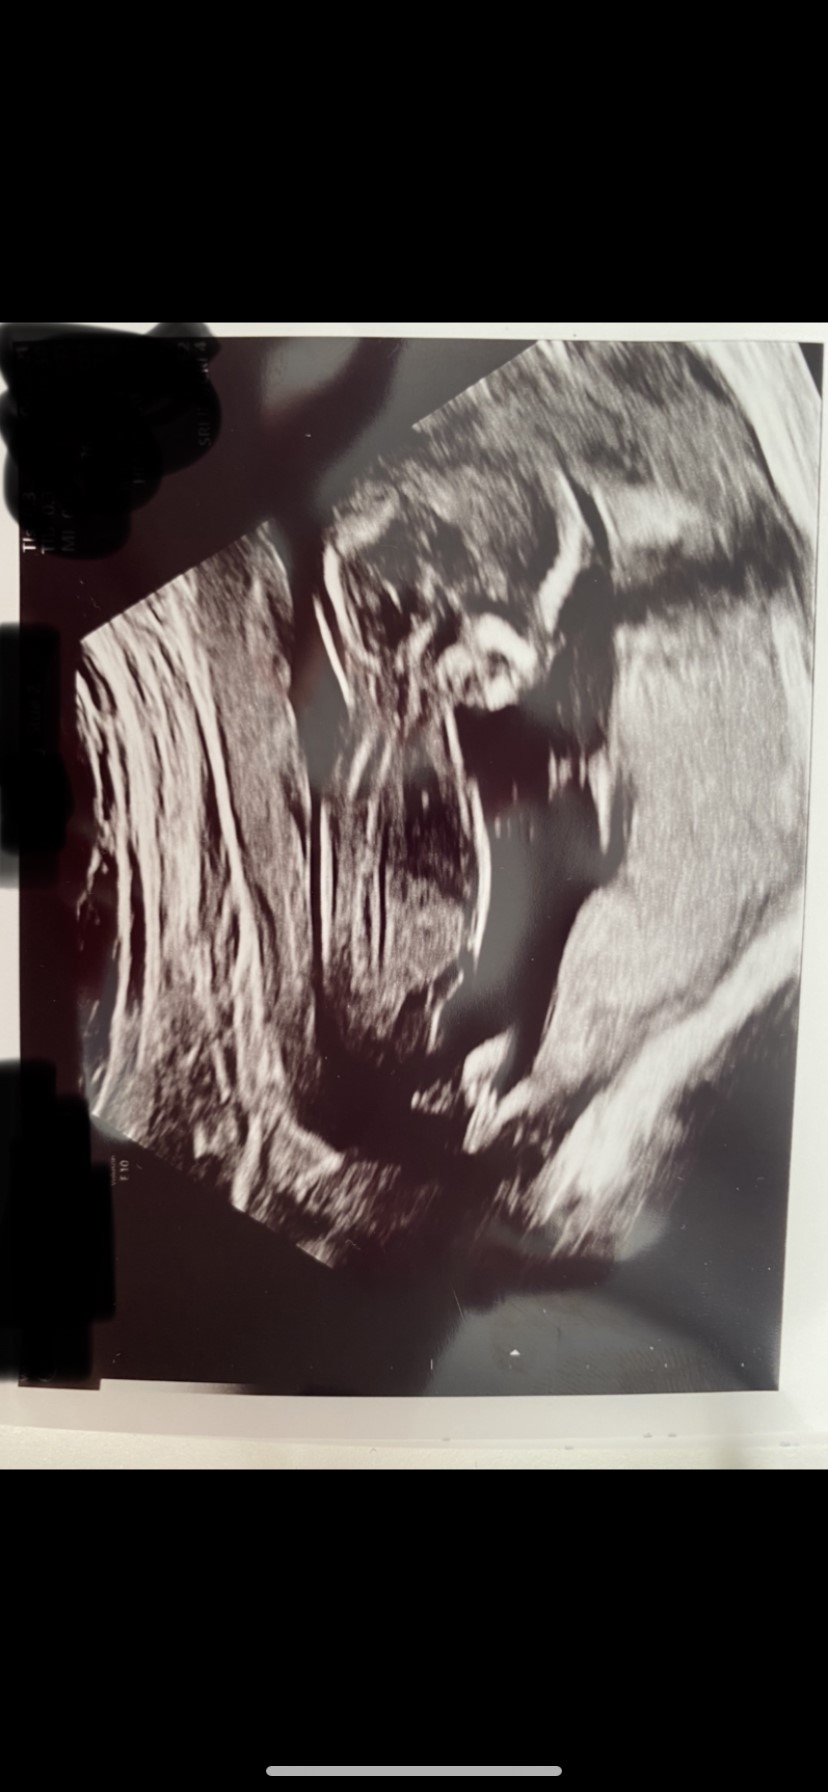

Hvad mon der gemmer sig derinde?

Vedhæftede fotos (klik for at se i fuld størrelse)

Jeg synes, det ligner en pige